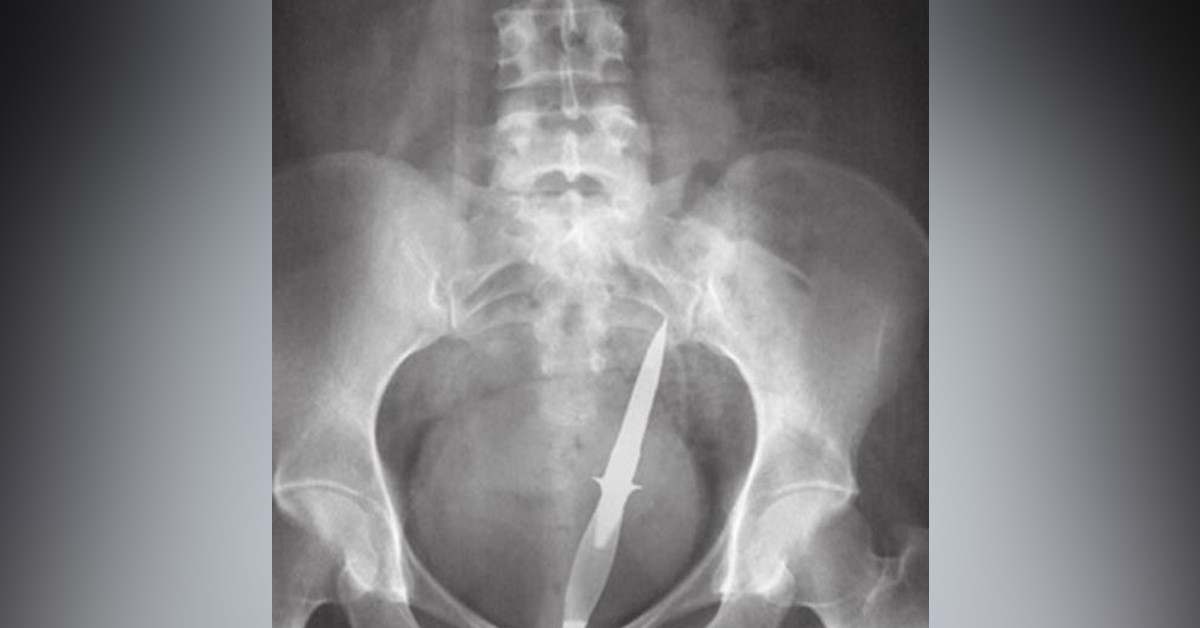

Özellikle hastanelerin acil bölümünde görev alan doktorlar karşılaştığı vakalar filmlere konu olacak türden. Çünkü sadece kazalar ve acil yaralanmalar değil, bunların dışında anlam vermesi güç tuhaflıkta vakalar da karşılarına çıkabiliyor. Bu röntgen filmlerini de bir hastane derleyip hasta isimlerini vermeden enteresan vakaları toplumla paylaşıp 'Sizce bunlar nasıl mümkün olabilir' sorusunu sormuşlar.

Görsellere bakıldığında anlamlandırması hakikaten zor olan bu durumları için 'Bu insanlar ne yaşıyor' sorusunu sorabiliyoruz.

Buyurun bu görsellere birlikte tekrar göz atalım.